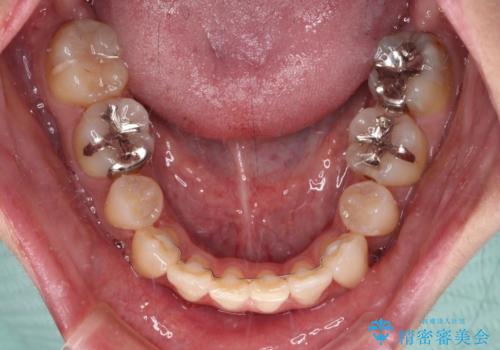

- 八重歯や前歯のデコボコを気にして来院された患者様です。

目立たない装置を希望されたので、上顎が裏側装置のハーフリンガルを選択し、上下左右の小臼歯(計4歯)を抜歯して矯正治療を行うこととしました。

補助装置を併用することで、八重歯を速やかに改善し、治療期間の短縮を図ることとしました。